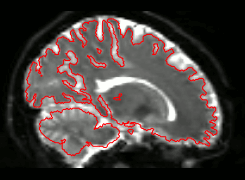

Quality Assessment

You should not trust any final outputs

WHY ?

DWI

FA

SSE

- One task - one QA

- General summary

- Global information

- Visual output

- Easy interface web-based